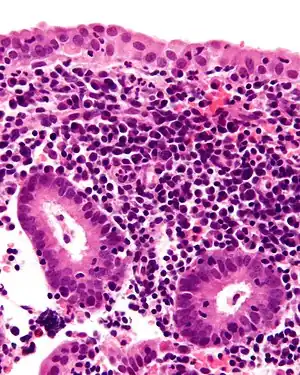

| Micrograph showing a chronic endometritis with the characteristic plasma cells. Scattered neutrophils are also present. H&E stain. | |

Chronic endometritis is characterized by the presence of plasma cells in the stroma. Lymphocytes, eosinophils, and even lymphoid follicles may be seen, but in the absence of plasma cells, are not enough to warrant a histologic diagnosis. It may be seen in up to 10% of all endometrial biopsies performed for irregular bleeding. The most common organisms are Chlamydia trachomatis (chlamydia), Neisseria gonorrhoeae (gonorrhea), Streptococcus agalactiae (Group B Streptococcus), Mycoplasma hominis, tuberculosis, and various viruses. Most of these agents are capable of causing chronic pelvic inflammatory disease (PID). Patients with chronic endometritis may have an underlying cancer of the cervix or endometrium (although infectious cause is more common). Antibiotic therapy is curative in most cases (depending on underlying cause), with fairly rapid alleviation of symptoms after only 2 to 3 days. Women with chronic endometritis are also at a higher risk of pregnancy loss and treatment for this improves future pregnancy outcomes.[17][18]